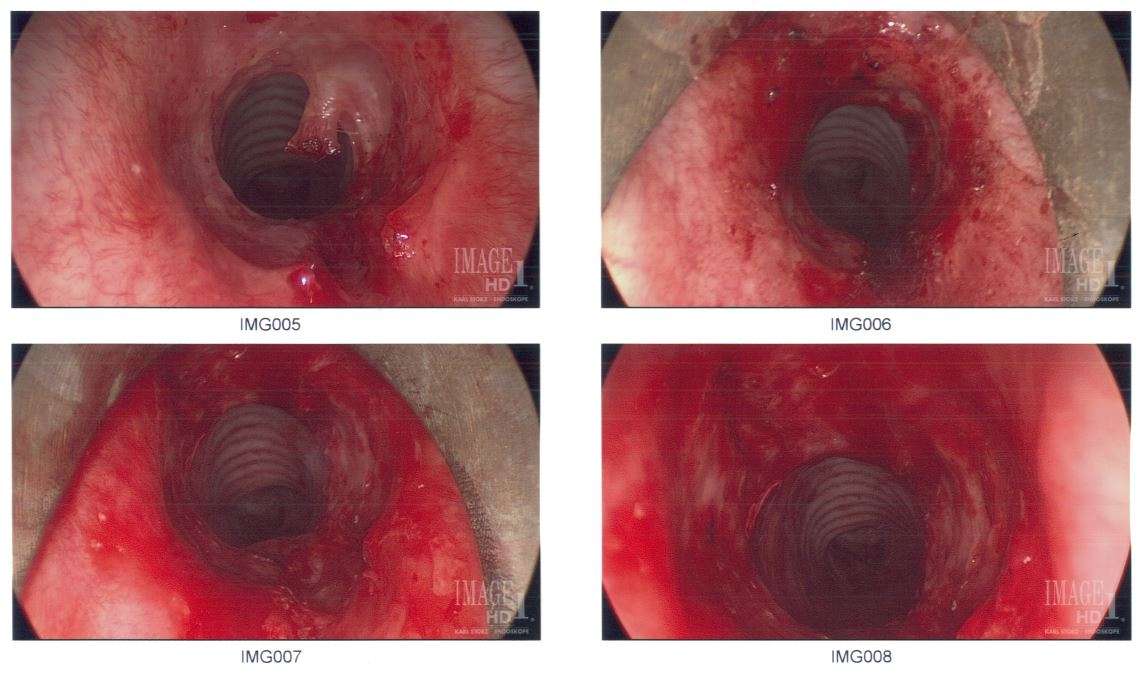

Subglottic stenosis is a congenital or acquired narrowing of the subglottic airway. Although it is relatively rare, it is the third most common congenital airway problem (after laryngomalacia and vocal cord paralysis). Subglottic stenosis can present as a life-threatening airway emergency. It is imperative that the otolaryngologist be an expert at dealing with the diagnosis and management of this disorder. Subglottic stenosis can affect both children and adults.

Subglottic stenosis can be of three forms, namely congenital subglottic stenosis, idiopathic subglottic stenosis (ISS) and acquired subglottic stenosis. As the name suggests, congenital subglottic stenosis is a birth defect. Idiopathic subglottic stenosis is a narrowing of the airway due to an unknown cause. Acquired subglottic stenosis generally follows as an after-effect of airway intubation, and in extremely rare cases as a result of gastroesophageal reflux disease (GERD).

Subglottic stenosis is graded from one to four based on the severity of the block.

Grade 1 - <50% obstruction, Grade 2 - 51-70% obstruction, Grade 3 - 71-99% obstruction, Grade 4 - no detectable lumen.

Treatments to alleviate the symptoms of subglottic stenosis includes a daily dose of steroids such as prednisone, which reduces the inflammation of the area for better breathing. Other medications such as Methotrexate is also being tested by patients but results are pending.